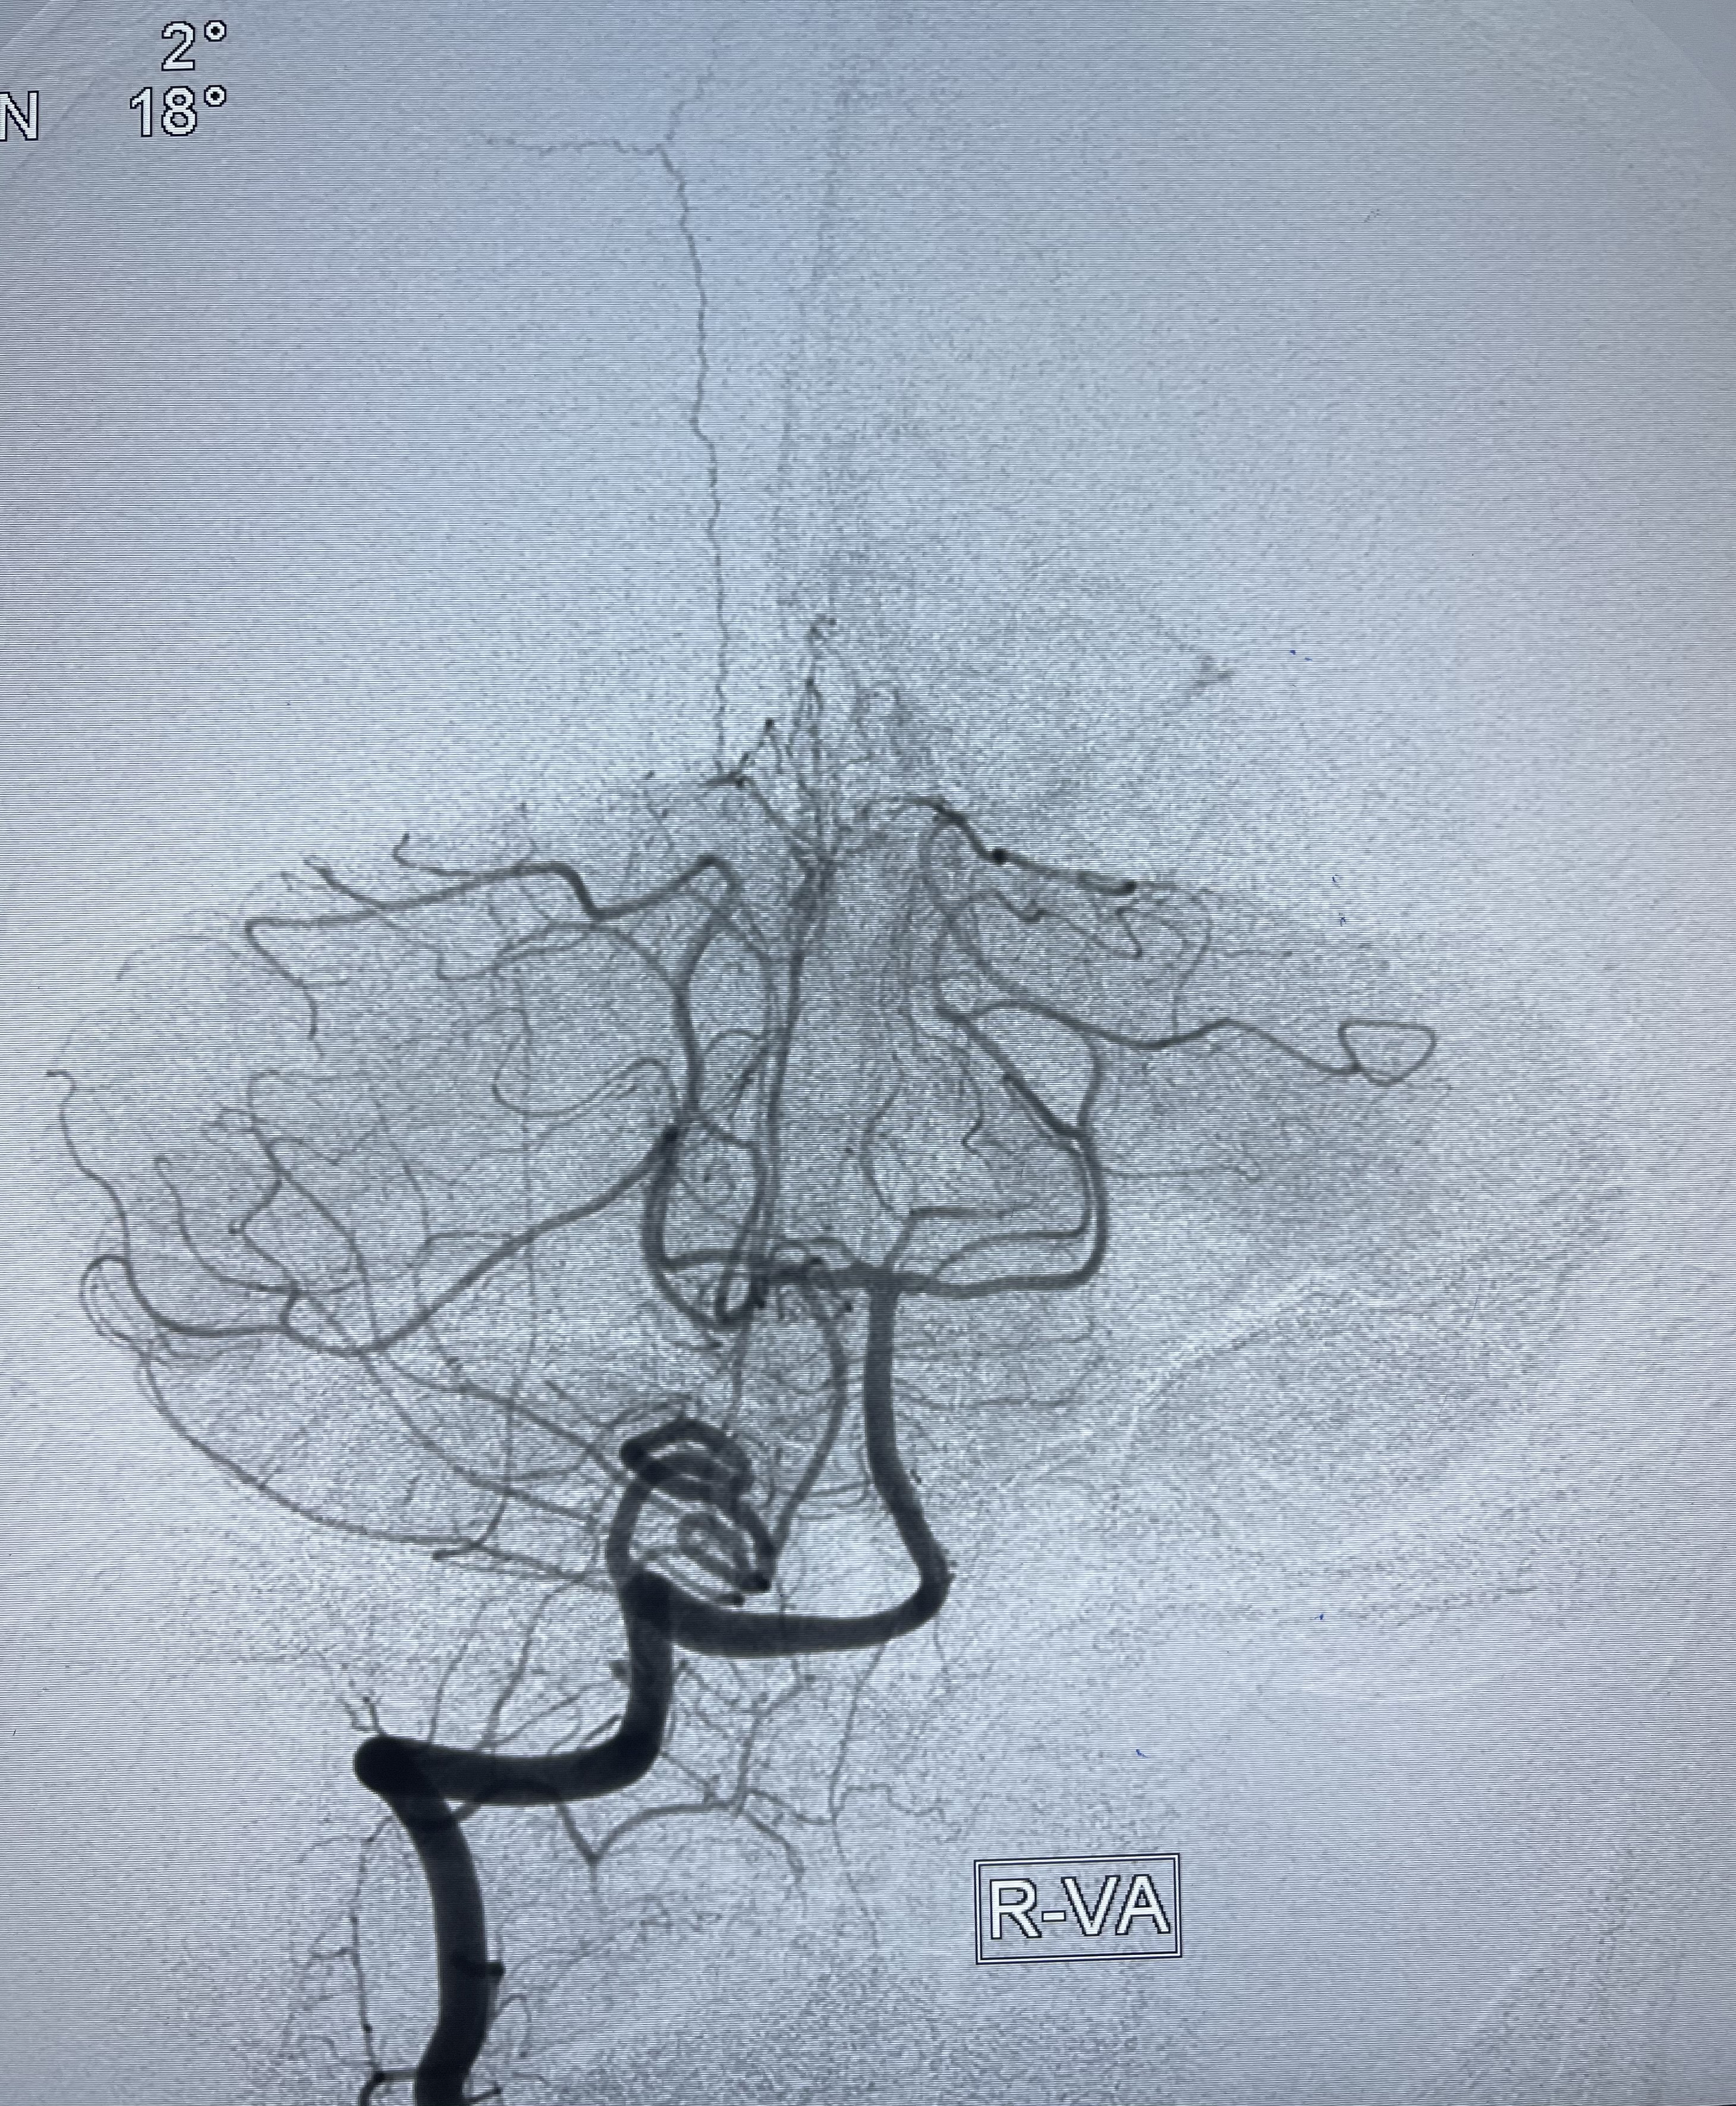

2021-01-07DSA

右侧前交通动脉瘤

箭头所示为左侧A2发出